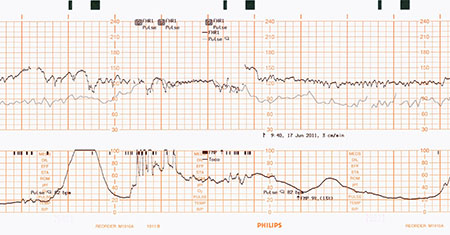

El monitoreo fetal electrónico proporciona información valiosa sobre el estado de salud del feto. Sin embargo, a veces, el pulso de la madre se confunde con la frecuencia cardíaca del feto, un error que se conoce como ambigüedad de la señal de la frecuencia cardíaca materna o inserción maternal. Cuando esto sucede, ciertos problemas del feto pueden pasar desapercibidos. La tecnología Smart Pulse distingue entre el pulso de la madre y el ritmo cardíaco del feto sin necesidad de un sensor adicional de SpO2 y ECG.

En la mayoría de los casos, el sistema de monitoreo fetal detecta fácilmente la frecuencia cardíaca del feto. En algunos casos, como cuando el feto no tiene frecuencia cardíaca o si un vaso de la madre está sobre el corazón del feto, se puede confundir el pulso de la madre con la frecuencia cardíaca del feto. En especial, cuando la madre está estresada y su pulso se eleva, este adopta una frecuencia similar a la del latido del corazón normal de un feto. Este pulso elevado hace que sea difícil para el profesional de la salud distinguir las señales. Para evitar la ambigüedad de la señal ocasionada por la frecuencia cardíaca de la madre, los monitores realizan una detección de coincidencias. La detección de coincidencias compara continuamente el pulso de la madre o su ritmo cardíaco, derivado de las mediciones del SpO2 o el ECG, con la frecuencia cardíaca del bebé. Cuando las dos frecuencias coinciden, el sistema de monitoreo alerta al profesional de la salud. Todos los monitores para fetos Avalon de Philips realizan esta detección de coincidencias a través de una característica estándar, llamada verificación cruzada de canales (CCV). Si bien la detección tradicional de coincidencias es eficaz, requiere que las mediciones de SpO2 y el ECG se realicen con sensores o electrodos independientes. Esto puede ser incómodo para la madre, requiere trabajo adicional para el profesional de la salud y no siempre es parte del protocolo estándar del hospital.

Los médicos deben controlar minuciosamente la frecuencia cardíaca de la madre y del bebé durante el trabajo de preparto y el parto. Por desgracia, a veces, se puede crear confusión al distinguir entre los dos pulsos, lo que genera una situación en la que los médicos no se dan cuenta de que ya no monitorean el corazón del bebé. Smart Pulse mide el pulso de la madre sin cables, electrodos o sensores adicionales. Esta característica patentada aprovecha el transductor MP Toco, cuyo diseño único mide las contracciones y la frecuencia cardíaca de la madre. El transductor MP Toco tiene dos sensores que miden el pulso de la madre, justo debajo de la superficie de la piel, lo cual evita confundir las señales

La verificación cruzada de canales (CCV) a través del SpO2 o ECG y del Smart Pulse de Philips permite medir el pulso, ofrece mayor comodidad y facilita el uso.